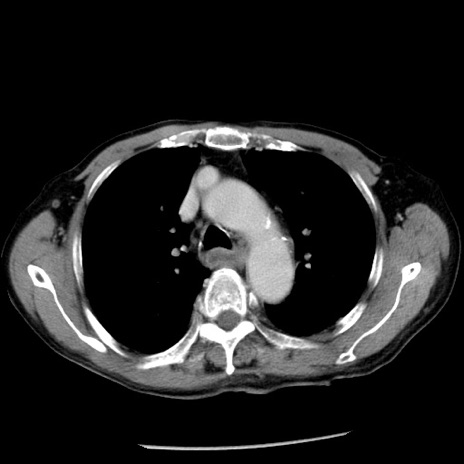

症例26(横断像)

【症例】80歳代男性

【主訴】嘔吐

【現病歴】昨晩2回嘔吐あり、今朝になっても嘔吐あり。来院。

【既往歴】胃潰瘍

【身体所見】意識清明、BT 37.6℃、BP 166/95mmHg、HR 100bpm、SpO2 97%、腹部:平坦・軟、腸蠕動音聴取良好、圧痛なし。

【データ】WBC 21900、CRP 1.46